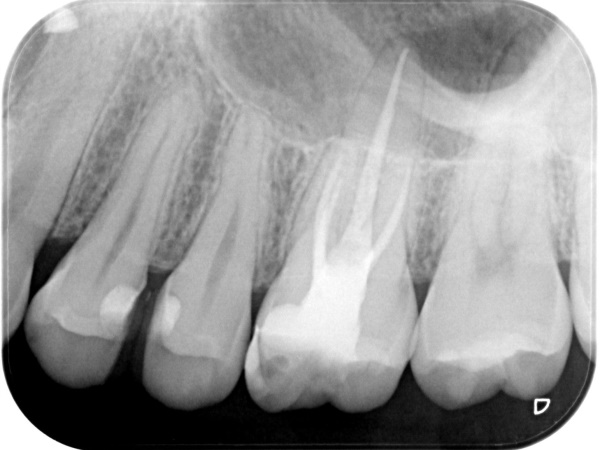

根管治療終了時